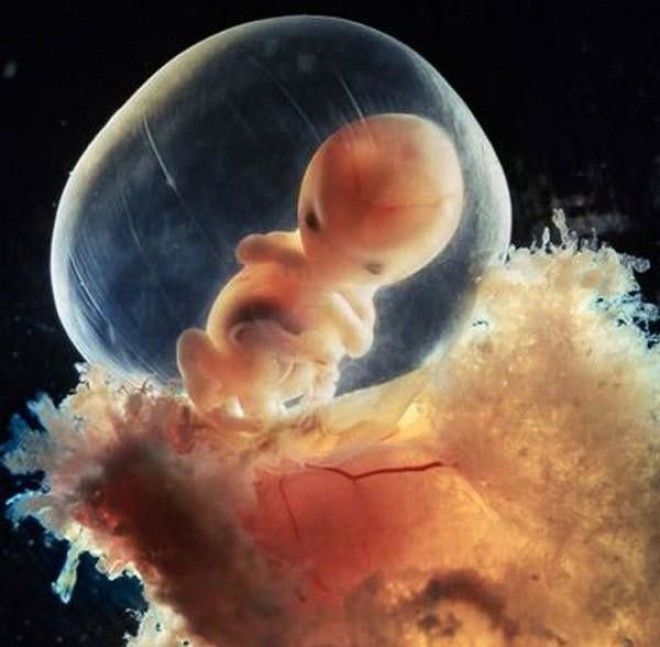

8 недель

10 недель. Веки уже полуоткрыты. В течение нескольких дней они сформируются полностью.